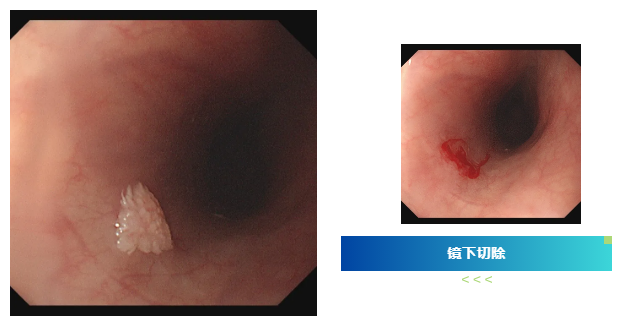

检查过程中,内镜医生有了意外发现:小张的食管部位长有一个形似花朵的乳头状瘤。吕主任介绍,食管乳头状瘤在临床中并不常见,尤其是在年轻男性群体中更为少见,其发病多与病毒感染相关,比如HPV病毒。幸运的是,发现及时,肿瘤尚处于早期阶段,医生随即为小张进行了内镜下切除术,整个过程顺利完成。